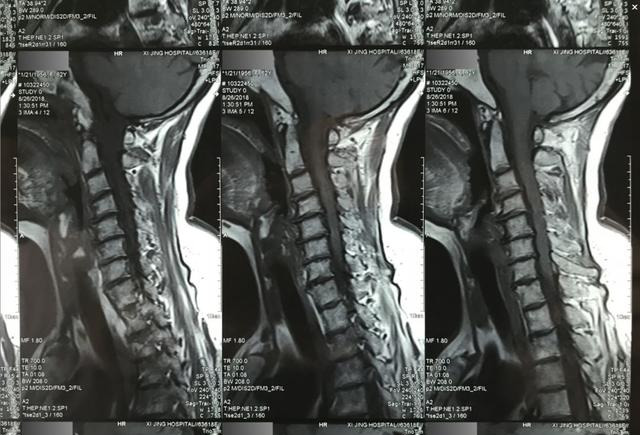

11。以序列进行分配的磁共振图像以获得以下相对有价值的清晰图片(图21-1,图21-2,图21-3,图21-4,图21-5,图21-5,图21-6,图21-7,图21-8)

(图21-1区域1)

(图21-2区域2)

(图21-3区域3)